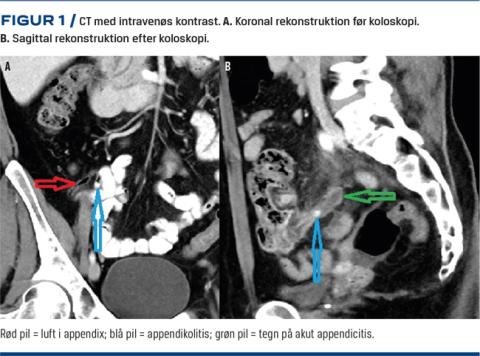

En 44-årig kvinde blev indlagt med mavesmerter, 24 timer efter at hun havde fået foretaget en ambulant koloskopi, som var et led i en klinisk kontrolundersøgelse fem uger efter en CT-verificeret akut sigmoiditis. Appendix var luftfyldt og reaktionsløs, og der blev påvist en appendikolitis distalt i lumen (Figur 1). Koloskopien blev gennemført uden komplikationer, og der blev påvist en stiv, ødematøs sigmoideum uden divertikler.

Få timer efter koloskopien fik patienten diffuse abdominalsmerter. Under den kliniske undersøgelse fandtes hun direkte og indirekte øm i højre fossa, men uden defence. Hendes temperatur var 37,9 °C. Man fandt leukocytose (15,0 × 109 leukocytter/l) og forhøjet niveau af C-reaktivt protein (87 mg/l). En CT af abdomen viste akut appendicitis med appendikolitis i basis af appendix.

Det særlige ved sygehistorien er, at der i sygdomsforløbet er foretaget to CT’er. Én kort tid før og én umiddelbart efter koloskopien. Begge CT’er blev udført med intravenøs kontrast, men uden barium givet peroralt, og ved koloskopien blev der ikke foretaget intubering af appendix. Den første CT viste en appendikolitis helt i toppen af appendix og ingen tegn på appendicitis. På den efterfølgende CT var der ingen appendikolitis i toppen, men en obstruerende appendikolitis i basis af appendix. Vores hypotese, på baggrund af den sparsomme litteratur på området, er, at appendikolitten blev displaceret under koloskopien, hvilket førte til akut appendicitis med begyndende symptomer efter få timer.